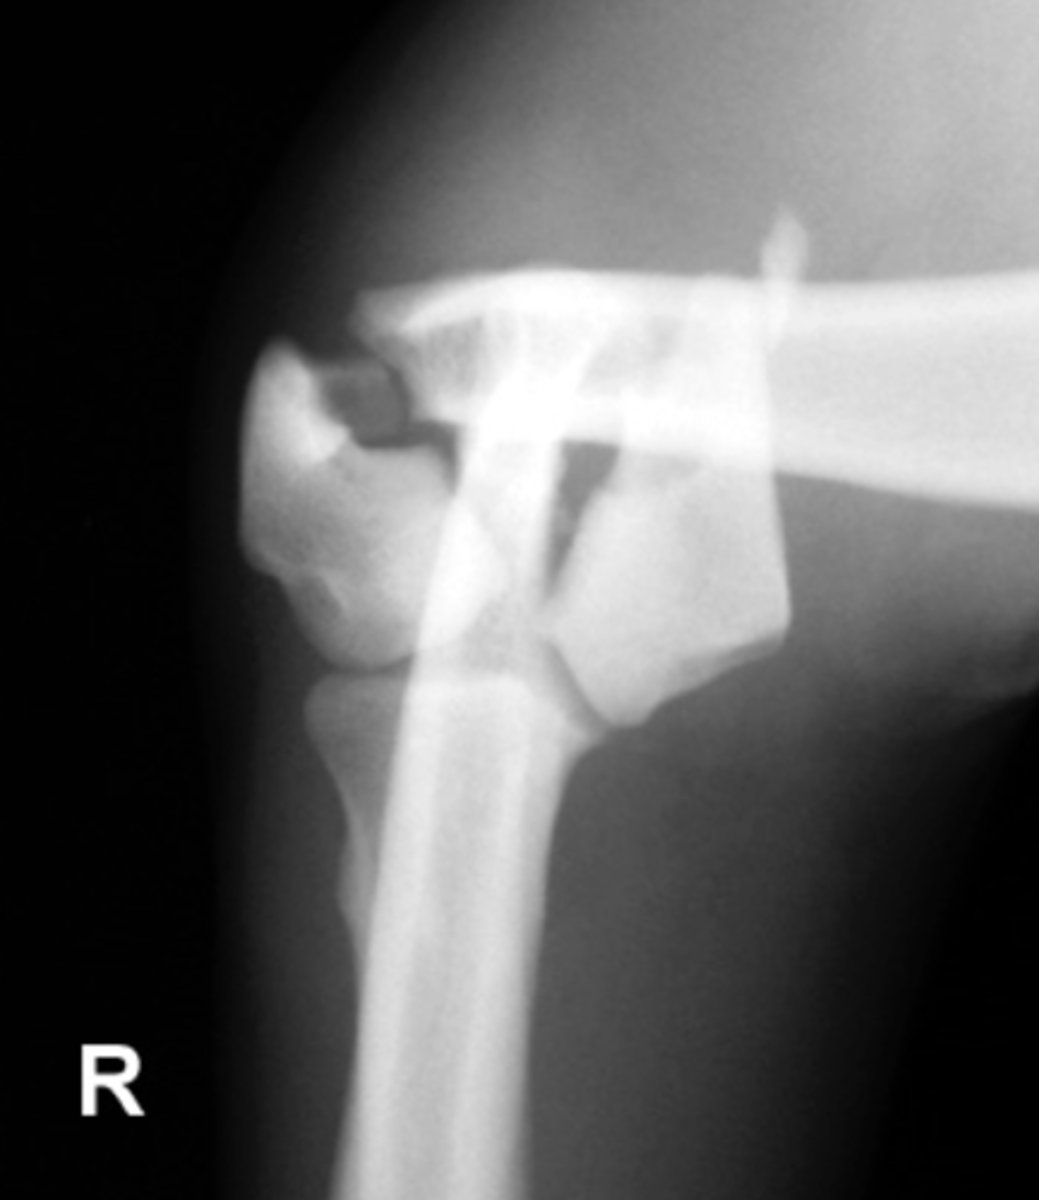

Grade the Salter-Harris fracture?

Grade 3 - fracture through the physis and epiphysis

beLow the physis

Grade 4 - fracture through the physis, epiphysis, and metaphysis

two or through